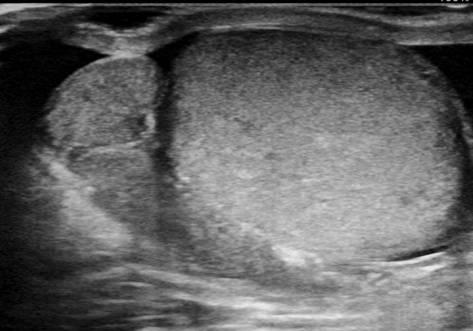

Viêm tinh hoàn - mào tinh

Viêm tinh hoàn – mào tinh

» Thông tin: Nam giới – 34 tuổi.

» Lâm sàng: Sưng đau vùng bìu.

# Tăng kích thước và tín hiệu mạch trên doppler tinh hoàn và mào tinh hoàn.